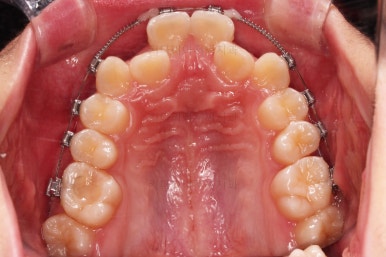

연산동치과 초진 시, 입안의 모습입니다.

보시다시피 앞니쪽이 많이 삐뚤고요. 어금니쪽이 긴밀하지 못한 부정교합이 있네요.

그리고 왼쪽 하단의 사진에 화살표를 보시면, 예전에 신경치료를 해둔 치아인데 어린 나이에 신경치료를 하다보니 크라운으로 치료를 마무리 하지 못했어요.